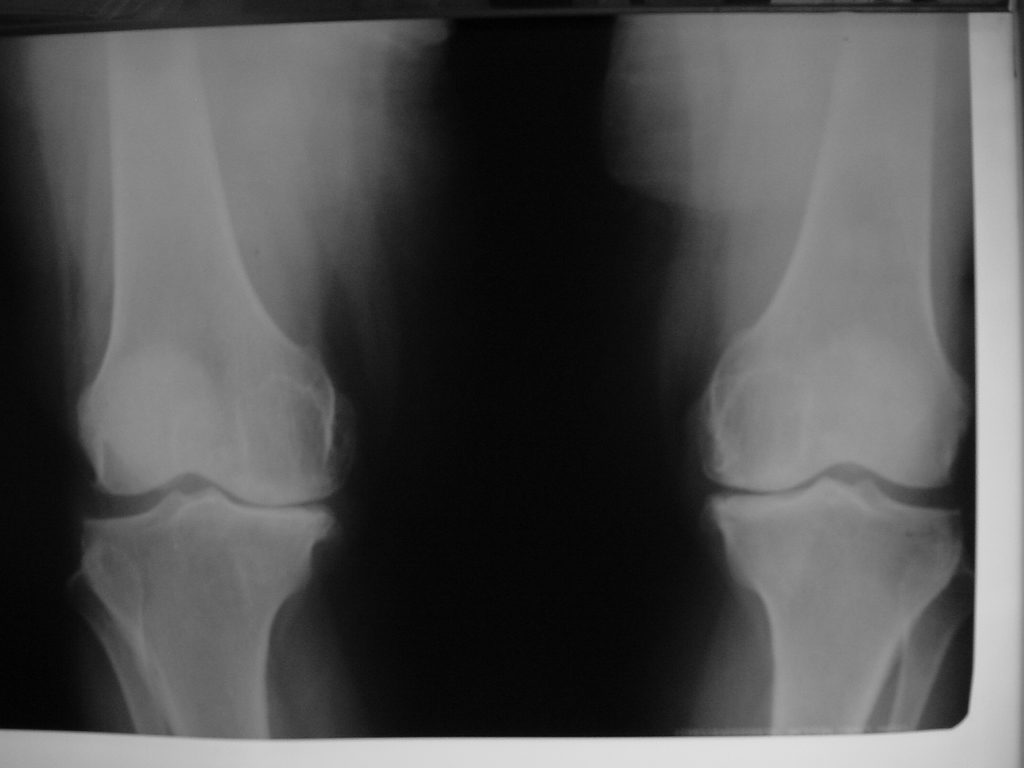

• Total Diz Protezi

• Total Diz Protezi Örnek Olgular